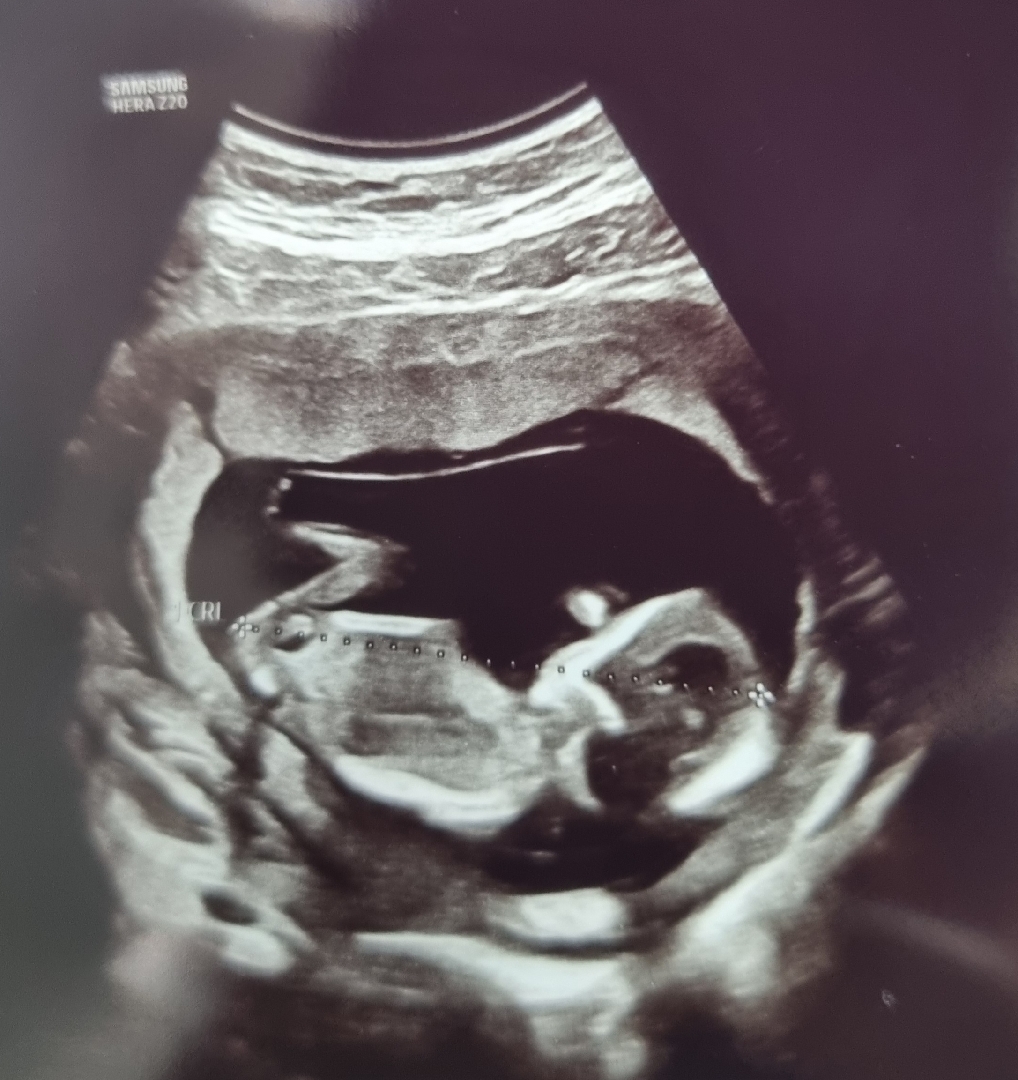

13주차 아기 성별 예측 도와주세요 ㅠㅠ

너무 궁금한데 전 잘 모르겠어요 ㅠㅠ

생식기가 안보이는 사진이라ㅠ 전 영상에서 생식기 두드러지는 부분 캡처해서 장꾸맘각도법 카페에 문의드렸었어요 ㅋㅋ AI도 장꾸맘님도 딸이랬고. 오늘 딸인거 확인 됐네요!! ㅎㅎ